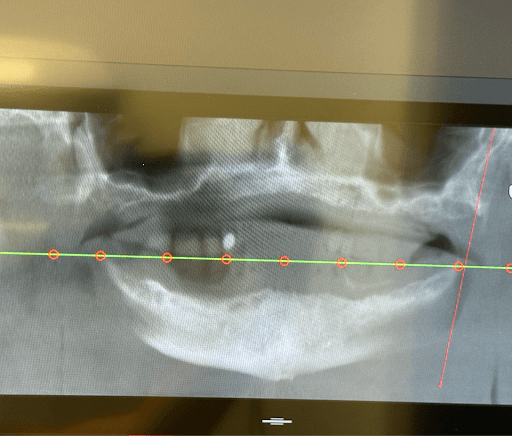

During clinical examination and CBCT evaluation it revealed severe maxillary atrophy (Cawood & Howell class V-VI), with reduced posterior bone height and unfavorable sinus pneumatization. The mucosa appeared thin but healthy, with no active infection. The mandible showed preserved basal bone and favorable ridge width posterior to the mental foramina.

Screenshot of imaging

x-ray

Imaging